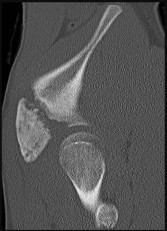

Figures 9a through 9d are the anteroposterior and lateral radiographs, CT scan, and technetium bone scan of a 12-year-old boy who has experienced 7 months of pain in his lower leg. The pain limits his ability to participate in sports and he is having difficulty sleeping. He is afebrile, and laboratory study findings including an erythrocyte sedimentation rate, C-reactive protein, and complete blood count are within normal limits.

The images and clinical history support a diagnosis of osteoid osteoma, which most commonly occurs in adolescence. Although these lesions can be seen in any bone, they are usually located in the femur and tibia. The significant inflammatory response to this tumor is secondary to high levels of prostaglandin production. Characteristic night pain is relieved with nonsteroidal anti-inflammatory drugs (NSAIDs) or by aspirin.

Radiographic images show thickened bone and a small central nidus. Thin-cut CT scan is the imaging of choice to visualize the nidus. A bone scan is associated with uptake but is not specific. Treatment options include expectant management with NSAIDs and observation under the premise that these lesions eventually burn out. Contemporary treatment involves RFA. Historically, these lesions were treated with en bloc resection; however, this technique has largely fallen out of favor because of the high efficacy and comparative low morbidity associated with RFA.

When an osteoid osteoma occurs in the spine, it is located in the posterior elements, and paraspinal pain and scoliosis often are present.